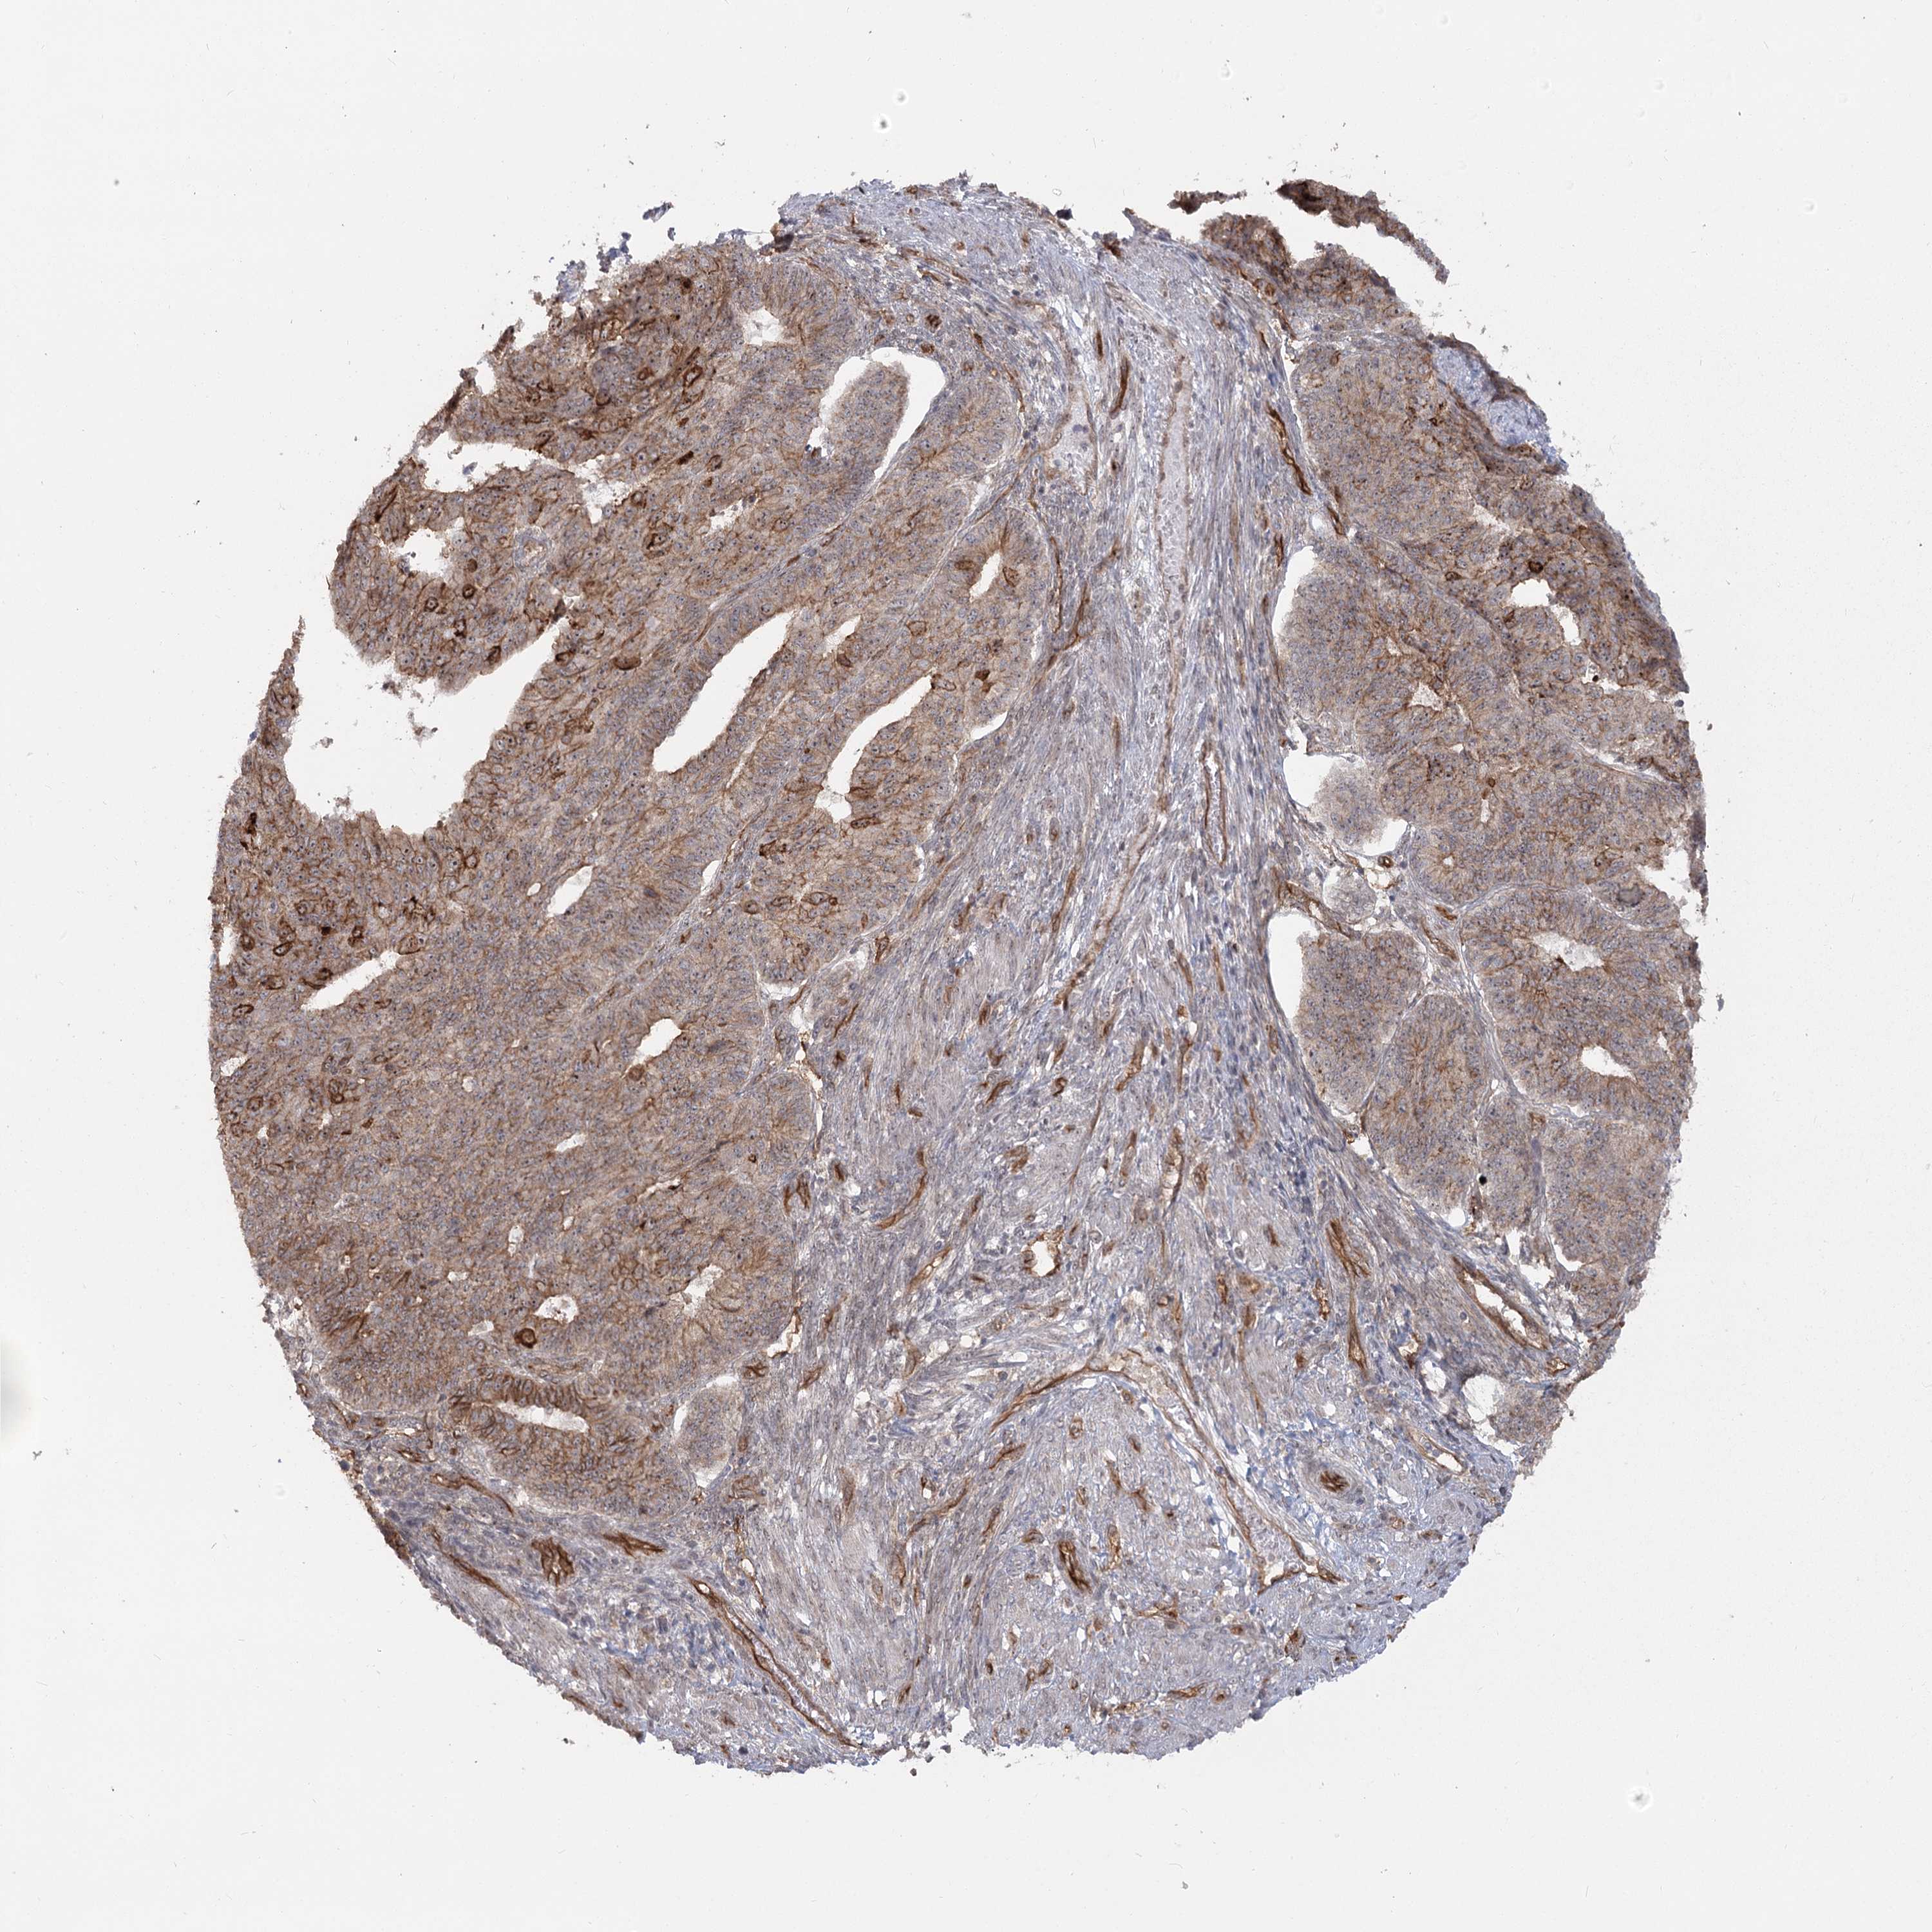

ENDOMETRIAL CANCER - Protein expressioni

A mouse-over function shows sample information and annotation data. Click on an image to view it in a full screen mode. Samples can be filtered based on level of antibody staining by selecting one or several of the following categories: high, medium, low and not detected. The assay and annotation is described here.

Note that samples used for immunohistochemistry by the Human Protein Atlas do not correspond to samples in the TCGA dataset.

Antibody stainingi

Antibody staining in the annotated cell types in the current human tissue is reported as not detected, low, medium, or high, based on conventional immunohistochemistry profiling in selected tissues. This score is based on the combination of the staining intensity and fraction of stained cells.

Each image is clickable and will lead to virtual microscopy that enables deeper exploration of all samples and also displays staining intensity scores, fraction scores and subcellular localization as well as patient and tissue information for each sample.

Antibody HPA036194

Staining

High

Medium

Low

Not detected

Intensity

Strong

Moderate

Weak

Negative

Quantity

>75%

75%-25%

<25%

None

Location

Nuclear

Cytoplasmic/membranous

Cytoplasmic/membranous,nuclear

Adenocarcinoma, NOS

Adenocarcinoma, metastatic, NOS